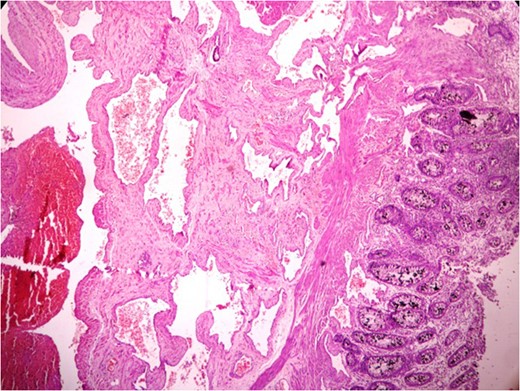

Thickened wall with tiny cystic spaces in mucosa, muscularis propria and serosa of the wall (inset: histopathological picture of the same area).

Anastomosing and dilated vascular channels in the submucosal area with congested and thrombosed blood vessels. (H&E ×400).

Histopathologically diagnosis of Cavernous Vascular Malformation—Diffuse infiltrating (expansive) type was given.